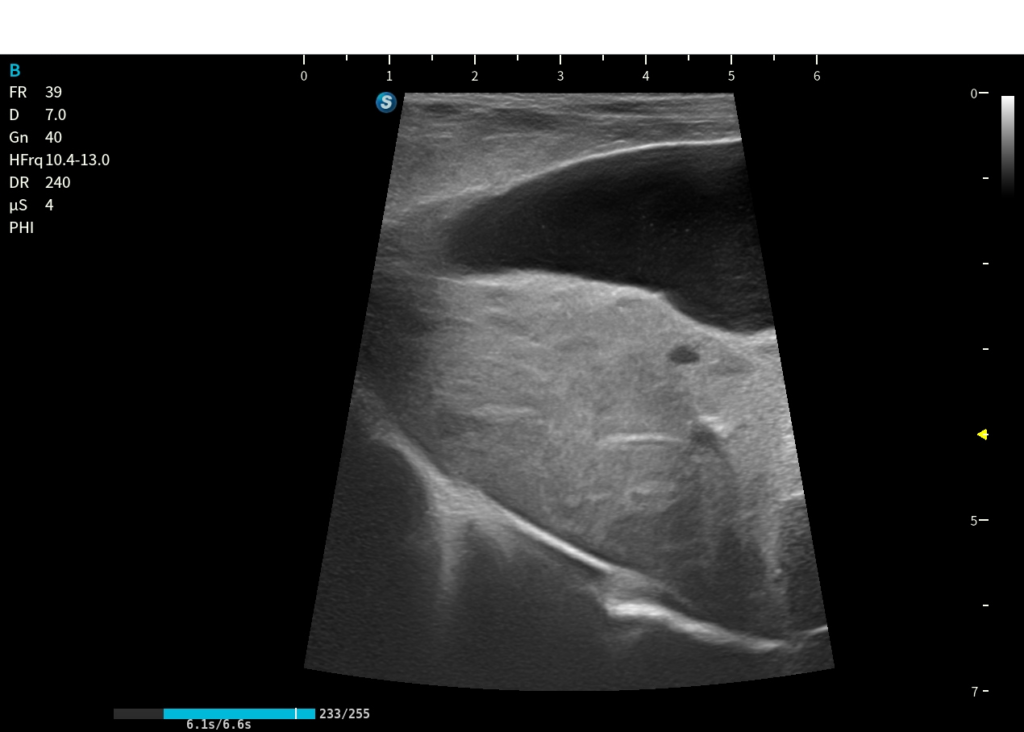

Pratica su cani vivi

Uno dei punti chiave del corso è la possibilità di esercitarsi su cani vivi, così da imparare la vera manualità.

Eco 5

Eco 4

Eco 3